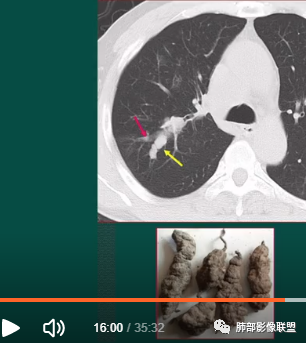

上图,小细胞肺癌,病灶从肺门朝外沿支气管爬行,呈指套样改变,病灶周围阻塞性肺炎较轻。

上图,支气管结石(红箭头),远端阻塞性炎症,腔内粘液栓。